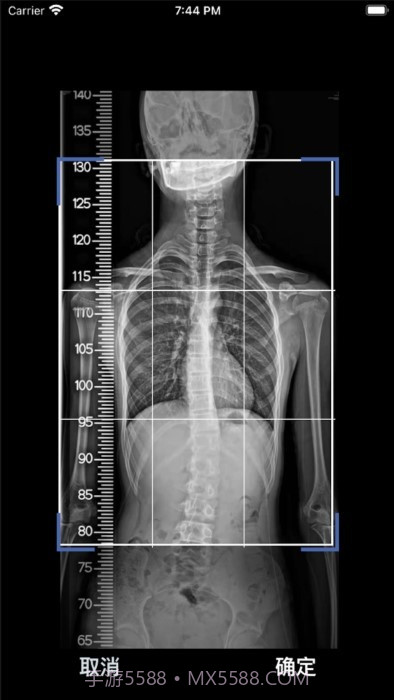

个人觉得,这款cobb角测量分析平台简直是医生和脊柱侧弯患者的福音!🌟 通过智能测量功能,能够迅速获取cobb角,准确率高得让人放心。对于有脊柱健康需求的小伙伴们来说,了解自己的状况特别重要,不仅能省时省力,更能随时存储和导出数据,后续分析也是轻松搞定!总之,这款应用为提高医疗效率、帮助患者掌握健康状况提供了强有力的支持,真心推荐给大家!

编辑点评:cobb角测量分析平台作为系统工具,这个应用的AI算法真的是一绝,相比其他同类工具更智能!,值得推荐。